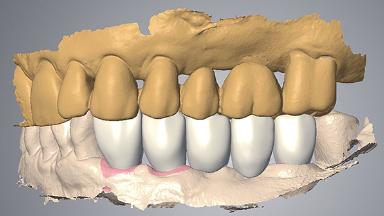

A 60-year-old healthy male patient presented with problems involving a fixed dental prosthesis (FDP) in the lower left quadrant. The bridge had de-cemented from abutment teeth 33 and 35; tooth 33 was decayed, and tooth 35 had little structure remaining. Since removing the FDP spanning sites 33 to 38 would have compromised function and raised esthetic concerns, the possibility of immediate implant placement and provisionalization was investigated.